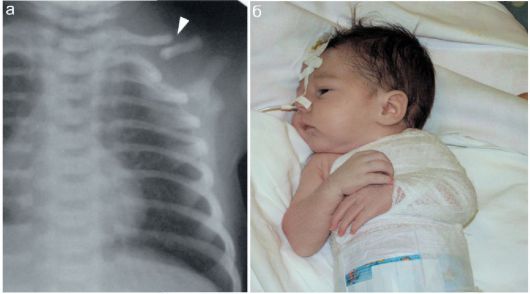

Диагностировать травму может врач-неонатолог. Основные признаки перелома включают:

- усиливающийся плач при прикосновении к ключице;

- отек и покраснение мягких тканей в этой области;

- сглаженная надключичная ямка;

- ограниченная подвижность руки (в тяжелых случаях);

- характерное похрустывание кости при пальпации (костная крепитация).

Если у пациента наблюдается значительная гематома, в течение трех дней следует лечить препаратом Канавит или витамином К, вводимым внутривенно. Аналогичная терапия назначается при вывихе ключицы. Для определения характера травмы необходимо сделать рентгеновский снимок.